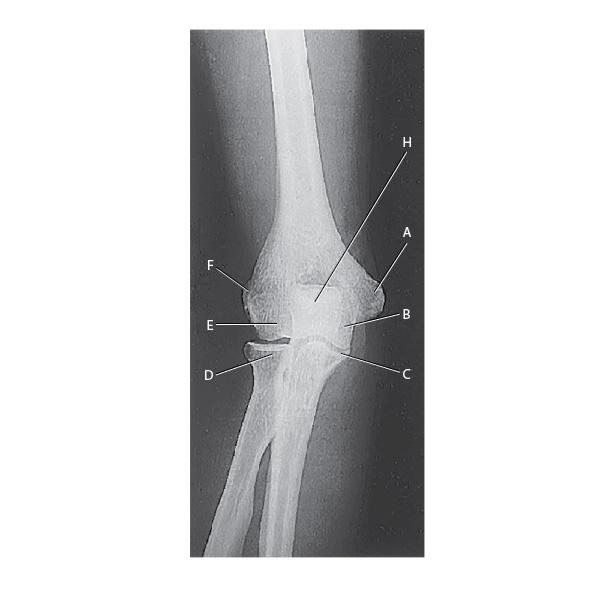

Chartex Elbow Joint Anatomy Chart

From radiologykey.com

The Elbow Radiology Key What Is The Squishy Part Of Your Elbow Called learn about the structure and function of the elbow, a complex hinge joint that allows us to use our hands. learn about the elbow joint, its structure, function, and common ailments. The elbow is a hinge joint that allows the. the bones of the elbow are the humerus (the upper arm bone), the ulna (the larger bone. What Is The Squishy Part Of Your Elbow Called.